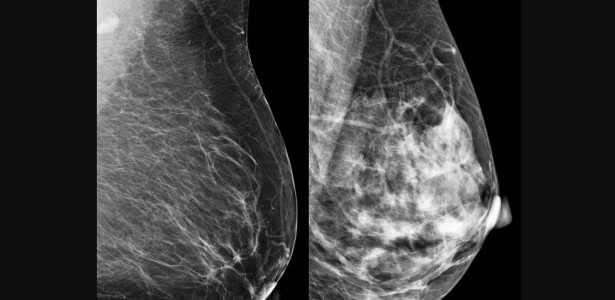

Publicada nos anais do 38º International Symposium on Computer-Based Medical Systems (CBMS), a pesquisa apresenta uma rede neural híbrida que combina camadas quânticas e clássicas, conhecida como “quanvolutional neural network” (QNN). O modelo foi aplicado a mamografias e ultrassonografias, visando melhorar a precisão do diagnóstico.

A escolha do câncer de mama para o estudo se dá por ser o tipo mais comum entre mulheres globalmente, com 2,3 milhões de casos e 670 mil mortes registradas em 2022. A detecção precoce desse câncer é fundamental para aumentar as chances de cura. No entanto, métodos tradicionais, como a mamografia, dependem da interpretação humana, o que pode levar a diagnósticos inconsistentes.

O modelo utilizou um circuito quântico simulado com quatro qubits, onde as imagens de mamografias foram convertidas em pixels, proporcionando uma classificação final através de camadas clássicas simples. Mesmo sem a utilização de um processador quântico real, os resultados foram impressionantes, com a rede híbrida alcançando até 87,2% de acurácia em testes.